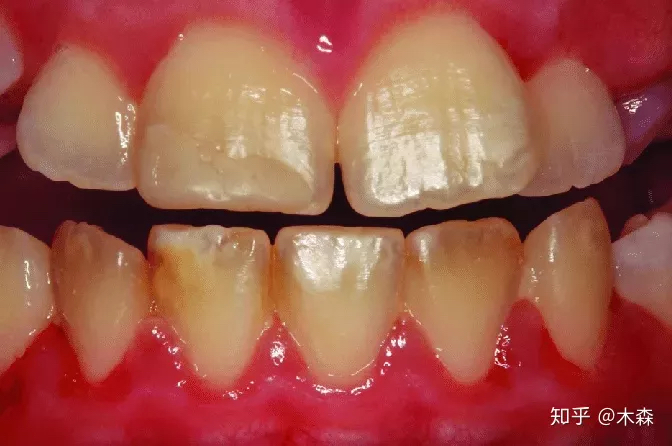

图:牙釉质1级缺陷,主要存在颜色上的改变 - Source:DOI: 10.4317/medoral.22506

第1级,牙釉质存在颜色上的缺陷。在牙齿上,可能存在单个或多个的奶油色、黄色或棕色的浊斑(边界清晰或模糊)。部分牙釉质可能缺乏透明度。

按照严重程度,牙釉质缺陷可分为不同的等级——1级为最轻微,4级为最严重。

依照Aine分类标准,牙釉质缺陷分为4级。